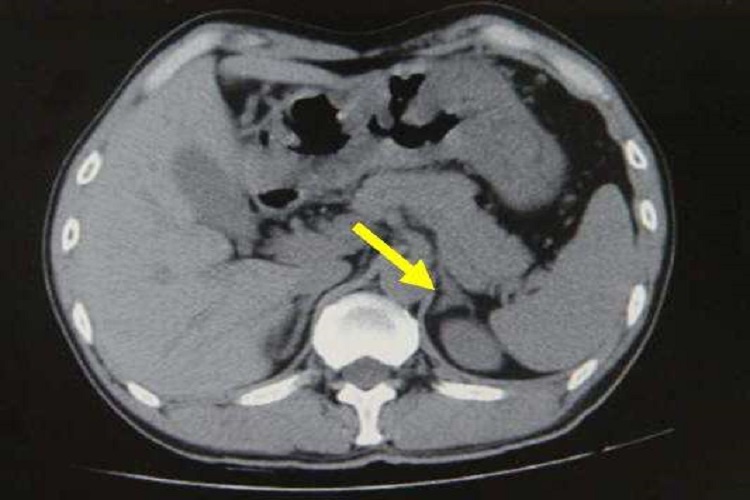

肾上腺肿块:双侧肾性肿块常见于肾上腺转移瘤,但也见于肾上腺结核、皮质腺瘤和嗜铬细胞瘤等。通常良性功能性肿瘤常较小,例如原发性醛固酮增多症和库欣综合征中的腺瘤,直径常分别小于2cm和3cm。肾上腺非功能性肿瘤和恶性肿瘤通常较大,例如肾上腺皮质癌发现时直径多大于6cm。肿块密度均匀水样低密度肿块,呈均一强化常为功能性腺瘤和非功能腺瘤。

肾上腺增大:即侧肢厚度大于10mm,边缘可有小的结节影,增大肾上腺的密度和外形正常,为肾上腺增生表现。